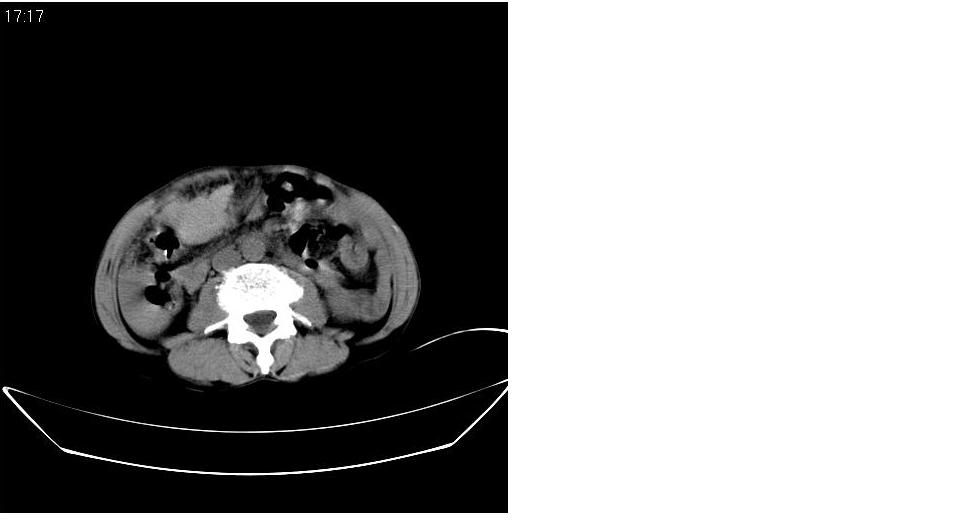

标题: CT20033:上腹部CT平扫

男 66岁,腹疼,b超提示考虑肝癌。

肝癌并门脉癌栓形成。

没完善检查手段,增强后再说,就算你有一万个理由说是肝癌,证据何在?

呼吁从事ct诊断的同志们,腹部占位,特别是肝脏病变没有平扫和三期增强检查,我们底气不足,拿什么来让临床医师信服我们。